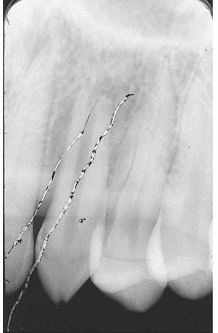

What is the problem with this STATIC ELECTRICITY X-ray?

Appears with thin, black, branching lines, Occurs when a film packet is opened quickly, Occurs when a film pack is opened before radiographer touches a conductive object

How would you resolve this STATIC ELECTRICITY X-ray?

Open film packets slowly, Touch a conductive object before unwrapping films when in a carpeted office